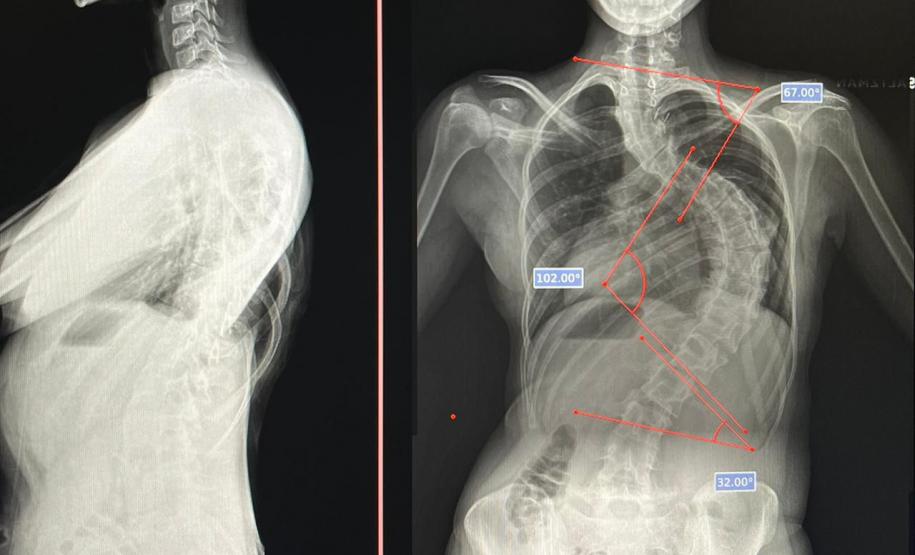

Outro tipo de escoliose é a causada por doenças neuromusculares, como paralisia cerebral, mielomeningocele, distrofia muscular, atrofia muscular espinhal, entre outras. No caso do Lucas Batista da Paixão, de 18 anos, a paralisia cerebral que teve ao nascer foi o que desencadeou a condição.

Com curvatura acima dos 100 graus, desconfortos respiratórios como falta de ar e asma, a posição do adolescente na cadeira de rodas estava bem limitada. Para a mãe de Lucas, Daniele de Oliveira Batista, a cirurgia foi fundamental para melhorar a autonomia e qualidade de vida do filho.